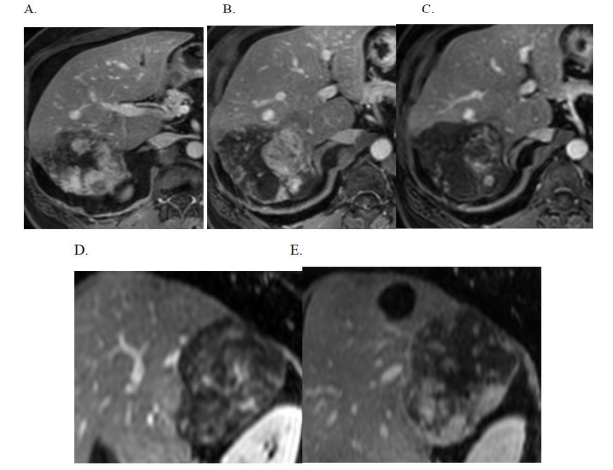

On the dynamic post contrast images the mass showed no enhancement on the arterial phase images (Figure 3). However on the portal phase (Figure 4) and venous phase (Figure 5) there were increased nodular and focal areas of enhancement. Delayed 10mins scan shows heterogenous enhancement of the mass (Figure 6A, B, C, D and E).

| Figure 6: (A, B, C, D and E) Delayed phase axial and sagittal images: Areas of heterogeneous enhancement with areas of non-enhancement |